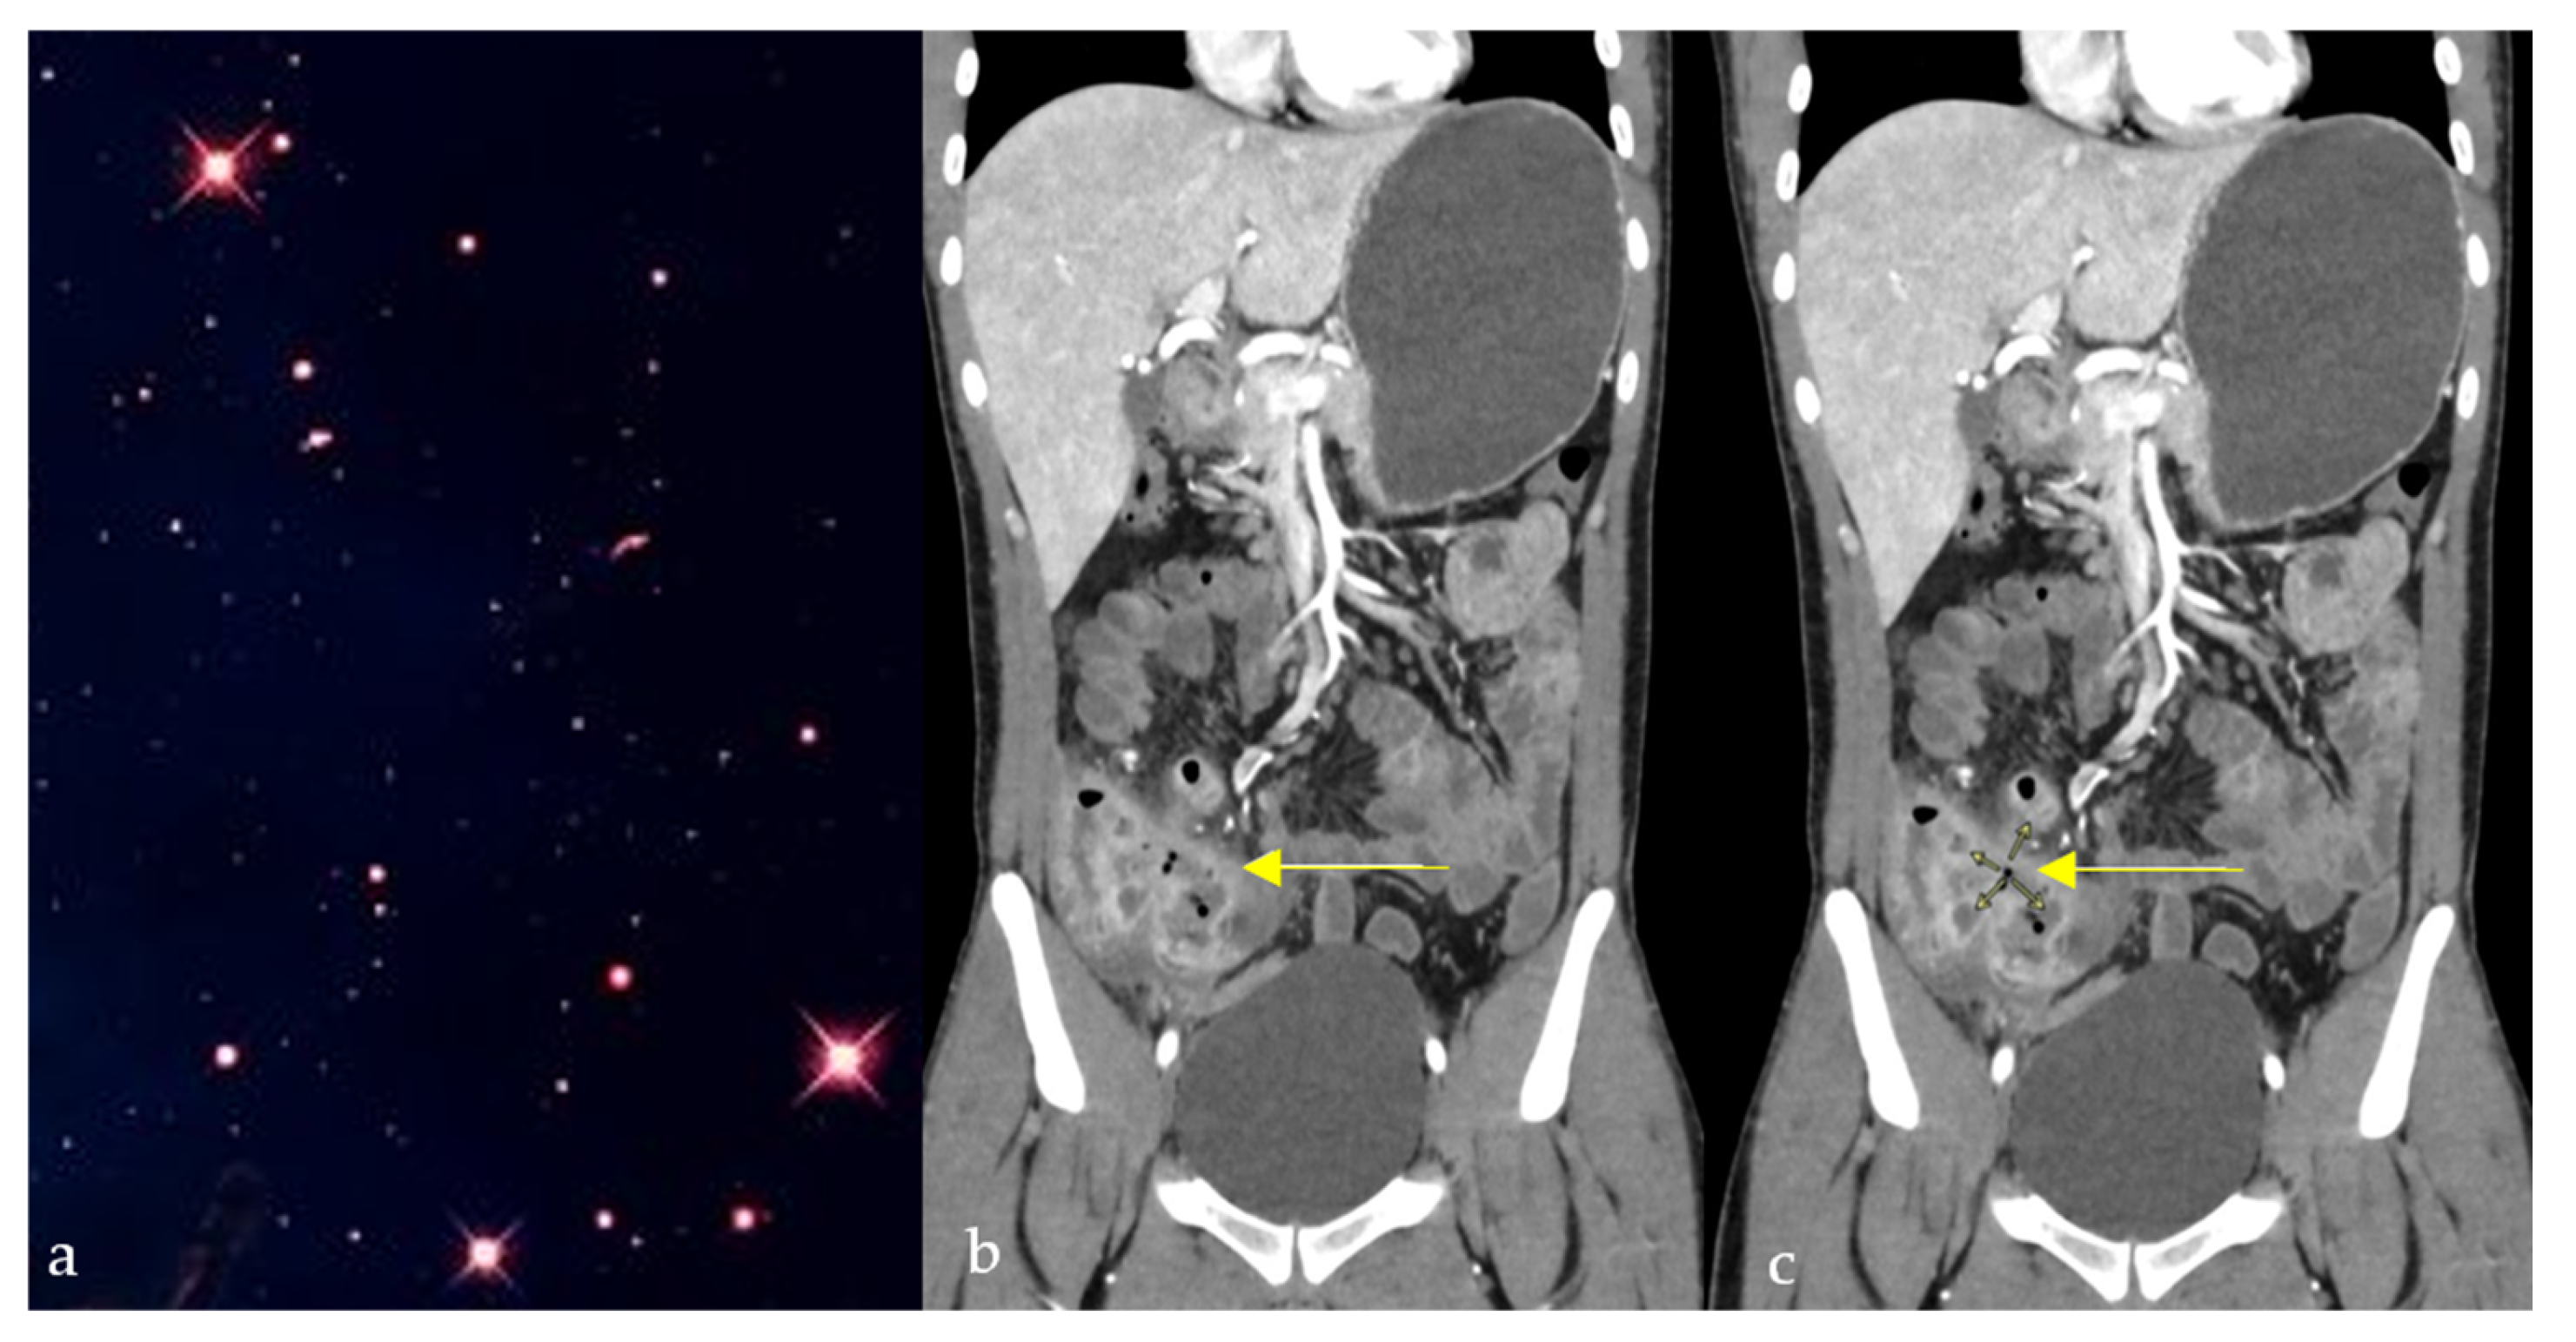

2.6. Starfield Pattern

- Brun-Vergara, M.L.; Montes, D. MRI of Cerebral Fat Embolism: Type 1 Starfield Pattern. Radiology 2020, 297, 303. [Google Scholar] [CrossRef]

- Parizel, P.; Demey, H.; Veeckmans, G.; Verstreken, F.; Cras, P.; Jorens, P.G.; De Schepper, A.M. Early Diagnosis of Cerebral Fat Embolism Syndrome by Diffusion-Weighted MRI (Starfield Pattern). Stroke 2001, 32, 2942–2944. [Google Scholar] [CrossRef]